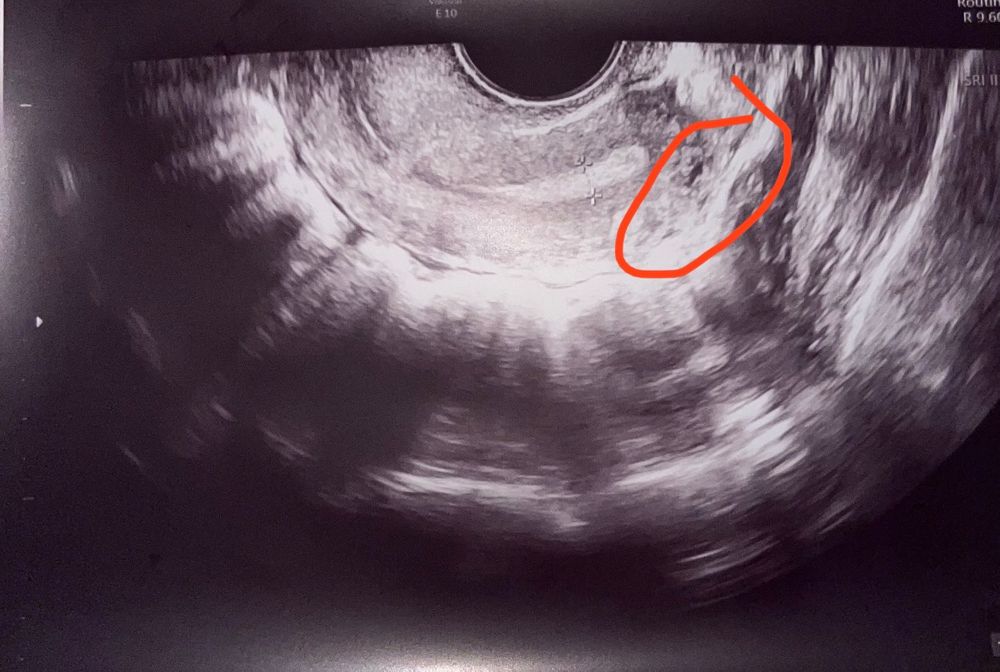

Это искажение узи. Ничего не значит. Сосуд попал в срез когда делали снимок эндометрия

На первом фото я так понимаю это матка что я обвела